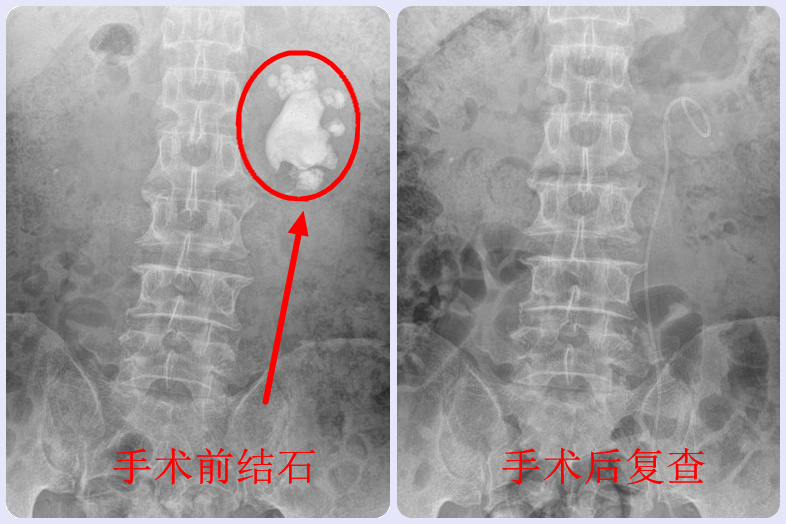

经过一系列的精心术前准备,江满涛带领团队成员如期对患者进行了手术。在彩超联合X光的引导下,用细针实施精准穿刺、扩张,建立起皮肤到肾脏的如筷子般粗细的微通道(直径约0.5厘米),然后用钬激光联合气压弹道碎石设备,通过该通道把肾内结石击碎并即时吸出,实现了巨大肾结石的微创治疗,同时手术中通过床边X光检查,发现无结石残留后结束手术。

江满涛表示,整个手术用时约2小时,而且出血很少,通过单通道一次性完美清石。目前,张先生已顺利康复出院。